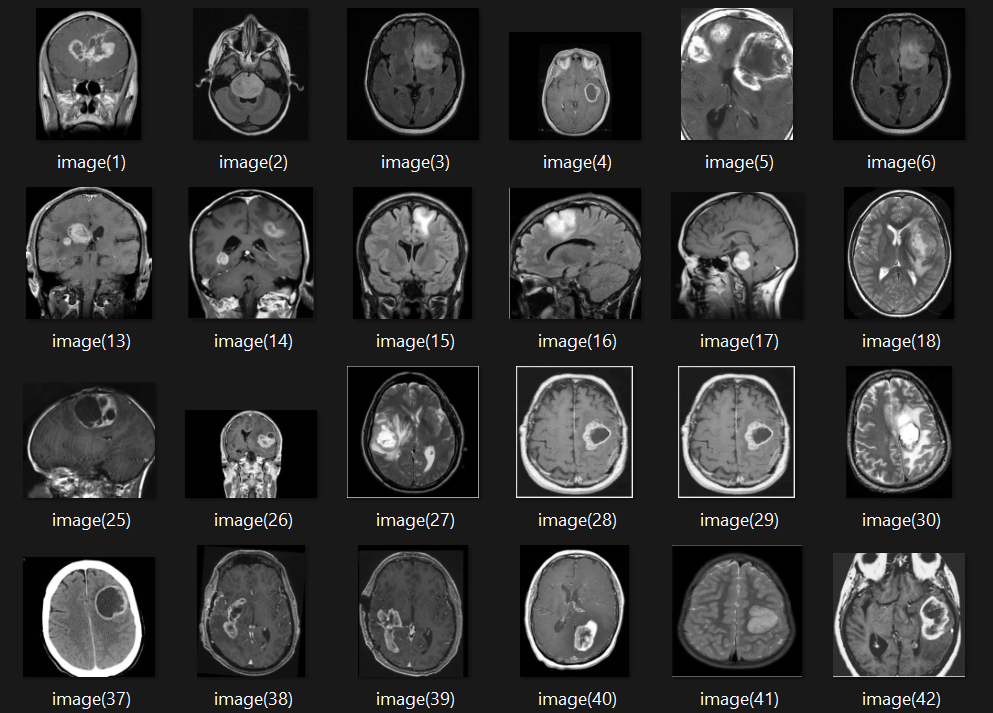

Brain Tumor Classifier

Machine Learning Healthcare

Classifies brain MRI images to detect tumors using machine learning models.